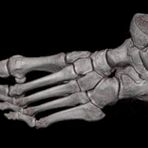

Extremitäten

• bei komplizierten Frakturen z. B. in der Nähe von Gelenken oder im Bereich der Handwurzel und Fußwurzel